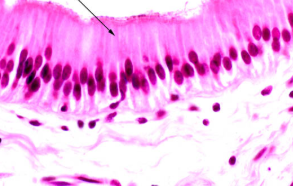

pseudostratified ciliated columnar

One layer but appear as more because so closely compacted together

Cilia on free surface

Nuclei found in different locations

Found in lungs, pharynx, trachea